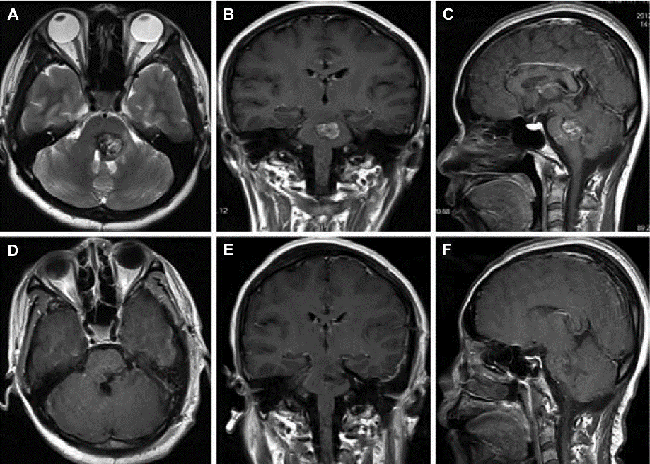

生长在脑干脑桥部位的海绵状血管瘤MRI影像

手术切除病灶是治疗海绵状血管瘤的根本方法。当患者出现明显的症状或者活动性出血(即使只有一次)的情况下,手术治疗是患者的选择。但当脑海绵状血管瘤位于脑干、脊髓、丘脑等被称为神经外科“手术禁区”的重要部位时,手术切除的难度会大大增加。比如脑干部位密布着颅神经核团、上行及下行纤维束以及网状纤维等,脊髓部位紧邻椎管内动脉,稍有不慎会有瘫痪、高位截瘫甚至死亡风险。